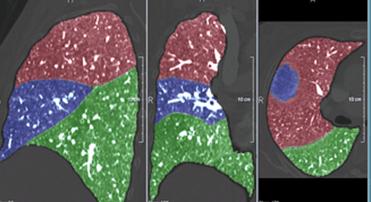

Quantificazione dell'enfisema mediante TC e software MeVisPulmo

Le TC sono state esaminate mediante l'impiego di un software (MeVisPulmo, Bremen) che consente la misurazione totale del volume polmonare, la densità media, i pixel, il "bulla index" e l'analisi sia qualitativa che quantitativa dell'enfisema polmonare. La valutazione prevede la segmentazione delle vie aeree e del polmone. I dati processati vengono storati come immagini DICOM (Digital Imaging and Communications in Medicine). Alla fine della processazione dei dati i valori vengono visualizzati e trascritti in un report. Le regioni lobari vengono indicate con differenti colori nelle sezioni sagittali, coronali e assiali come indicato nella fig. 3-5.

Figura 3. Scansione TC 3D (postero-anteriore). Albero

tracheobronchiale (azzurro), lobi inferiori (verde), lobi superiori

(rosso). I valori di pixels ≤ a -950 HU (giallo), identificano le

zone di enfisema.

Figura 5. Immagine assiale con ripartizione dei segmenti

polmonari indicati con colori diversi.